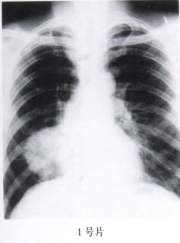

1.(1号片)

A、右肺周围型肺癌

B、纵隔肿瘤

C、右下叶肺不张

D、右下叶肺脓肿

E、右胸腔包裹性积液

答案:1—6:EDACAC 15—20:ACBDED

E、右胸腔包裹性积液「张博士医考www.guojiayikao.com整理,如有转载,请注明出处」